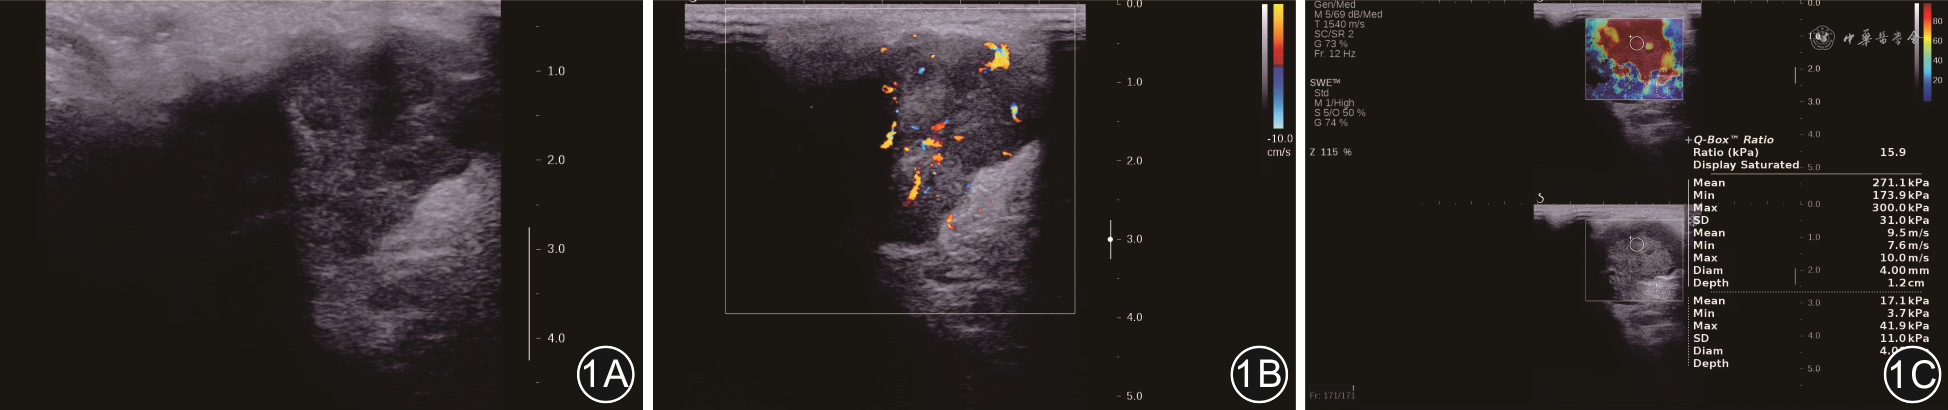

探头切换至Thyroid模式。先行常规超声检查。全面检查腮腺、下颌下腺区域及颈部淋巴结,观察有无肿瘤、肿瘤大小、解剖位置及声像图特点。再行彩色多普勒血流显像(color doppler flow imaging,CDFI)观察肿块内及周边血供特征,选取最清晰图像保存、记录。见图1。

先行常规超声检查。再切换探头至SWE模式,弹性取样框尽量包全肿块(以包含少量正常腺体组织为宜),嘱咐患者屏气,待图像完全充填、稳定3~5 s后冻结,通过Q-Box系统ROI(取直径4 mm)放置于肿块实质部分最硬区域(以弹性图像右上方彩色硬度标尺为参照:蓝色、软—红色、硬),测量并记录各弹性参数值,即平均弹性值(Emean)、最大弹性值(Emax)以及取样框内弹性数据离散度值(Esd),测量重复3次取平均值。见图1。